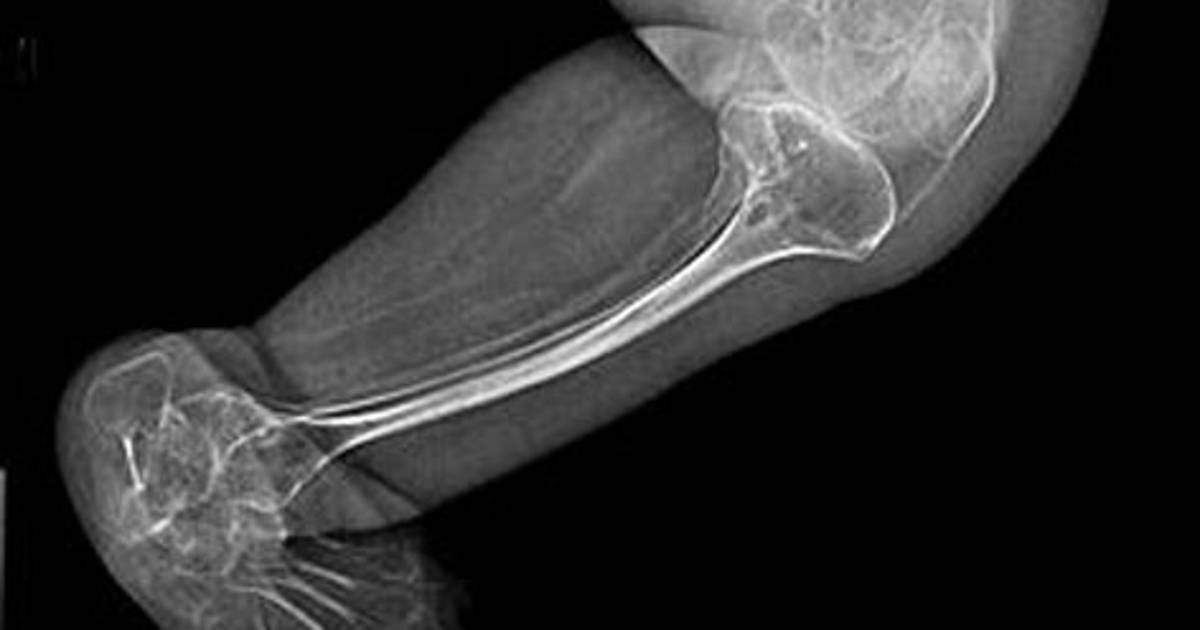

La enfermedad se caracteriza por una deficiencia en la producción de colágeno I, lo que provoca una fragilidad excesiva en los huesos

Esta enfermedad rara, comúnmente conocida como huesos de cristal, se caracteriza por una deficiencia en la producción de colágeno I, lo que provoca una fragilidad excesiva en los huesos.